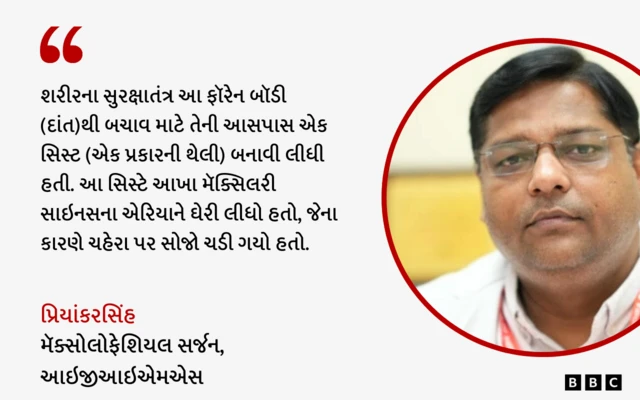

"શરીરના સુરક્ષા તંત્રે આ ફૉરેન બૉડીથી બચવા માટે તેની આસપાસ સિસ્ટ (એક પ્રકારની થેલી) બનાવી લીધી હતી. આ સિસ્ટે સમગ્ર મૅક્સિલરી સાઇનસના એરિયાને ઘેરી રાખ્યો હતો, જેના કારણે ચહેરા પર સોજો થઈ ગયો હતો અને ઉપરના જડબાનું હાડકું ગળી રહ્યું હતું."